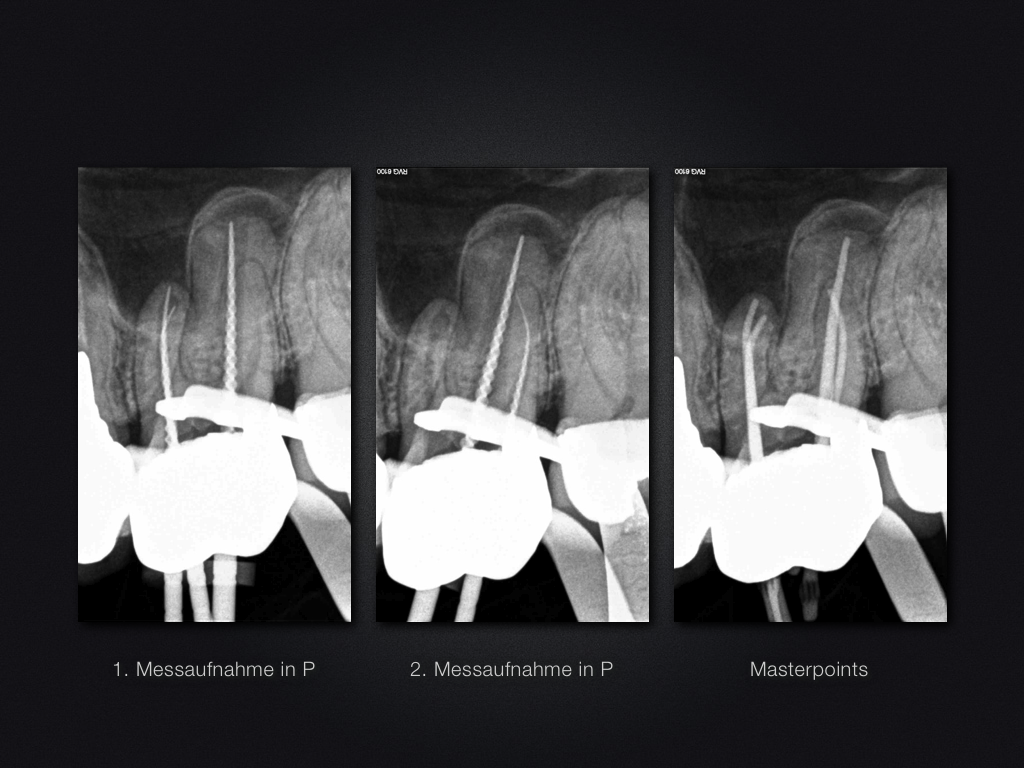

26D.004

All Inclusive